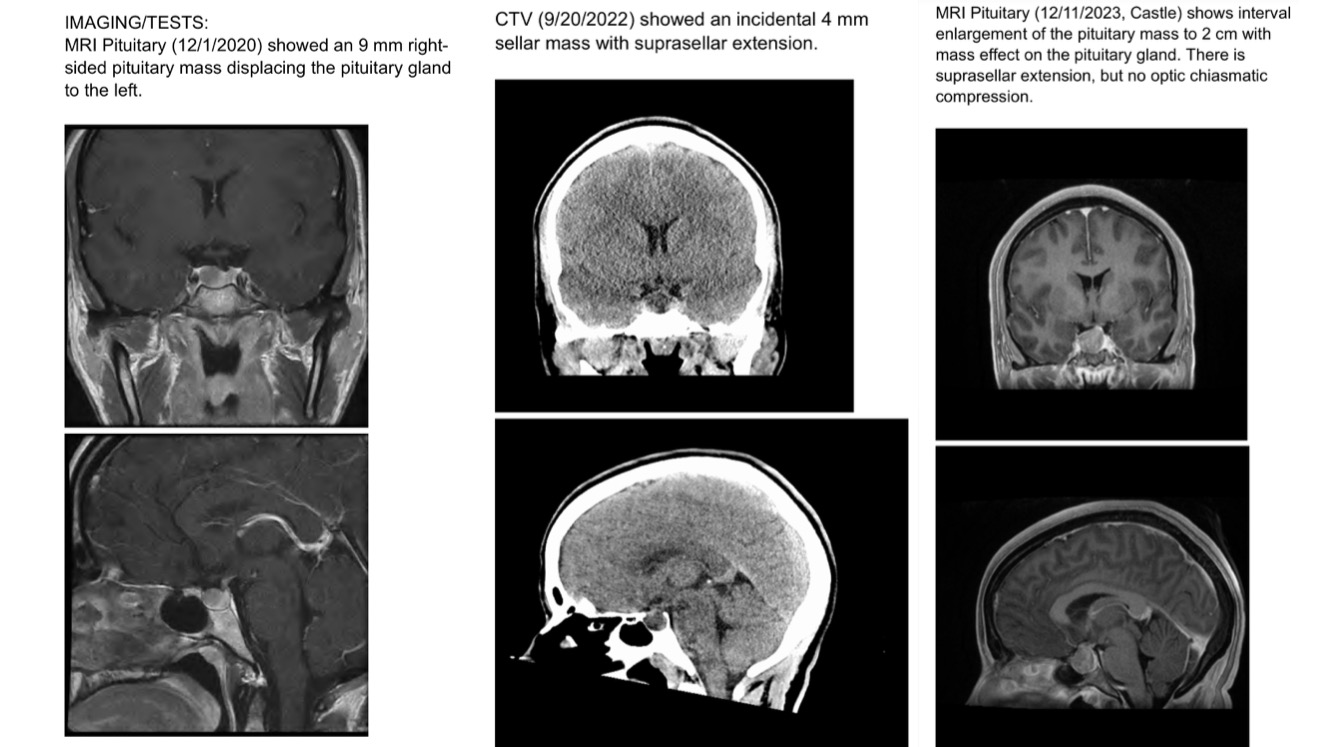

My name is Danielle, I just recently found out that I need brain surgery to remove a non-cancerous tumor that has been growing next to my pituitary gland for the last four years. I've been dealing with extensive medical issues and mystery symptoms for years now, and have been trying so hard to put all the pieces together and help my doctors and specialists find the root cause. I've gone to endocrinologists, neurologists, migraine specialists, physical therapists, my primary care doctor (and more) and have had MRIs, CT scans, EMG muscle tests, nerve conduction studies, many blood tests, and more to try to figure out what's been going on.

The tumor is called a pituitary adenoma and I'll be getting a Transsphenoidal Hypophysectomy to remove it. Pituitary adenomas cause hormonal spikes and dips and can cause migraines, vision problems, and more if not taken care of. My latest tests show that my growth hormone, IGF-1, is elevated and causing my bones to grow and my joints to be in pain all the time. This is also the reason my arm and legs experienced extremely painful nerve symptoms after getting the second dose of the vaccine and having an inflammatory response. I've also experienced debilitating migraines and had a low level headache everyday for at least the last four years. It's been a lot of work and super challenging at times to get doctors to take me seriously and to find root causes for my symptoms. I'm so happy I finally have a diagnosis and treatment to hopefully improve my symptoms.